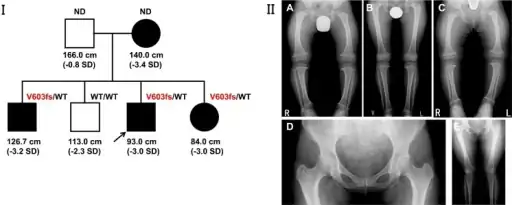

a-c) Three siblings demonstrated metaphyseal irregularities hip/knee, coxa vara, bowlegs. d-e) the mother demonstrated coxa vara

Unlike other "rickets syndromes", affected individuals have normal serum calcium, phosphorus, and urinary amino acid levels. Long bones are short and curved, with widened growth plates and metaphyses.[5]